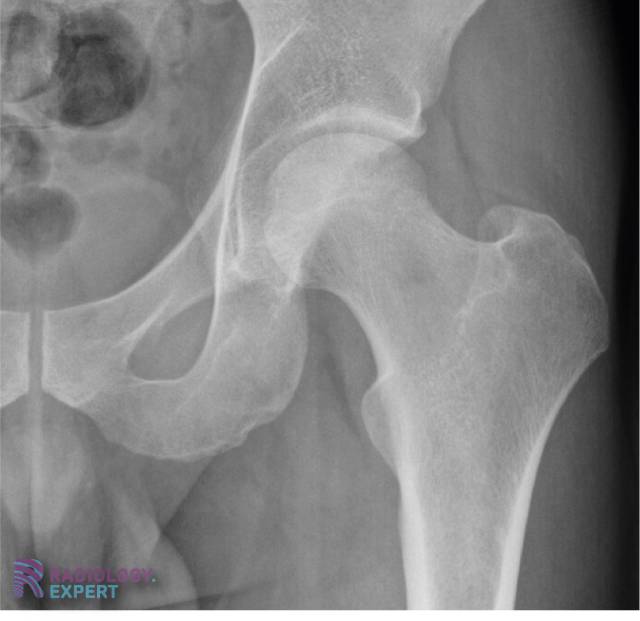

Normale anatomie X-heup (AP opname) Normale anatomie X-heup (AP opname)

Klik op afbeelding om overlay te zien